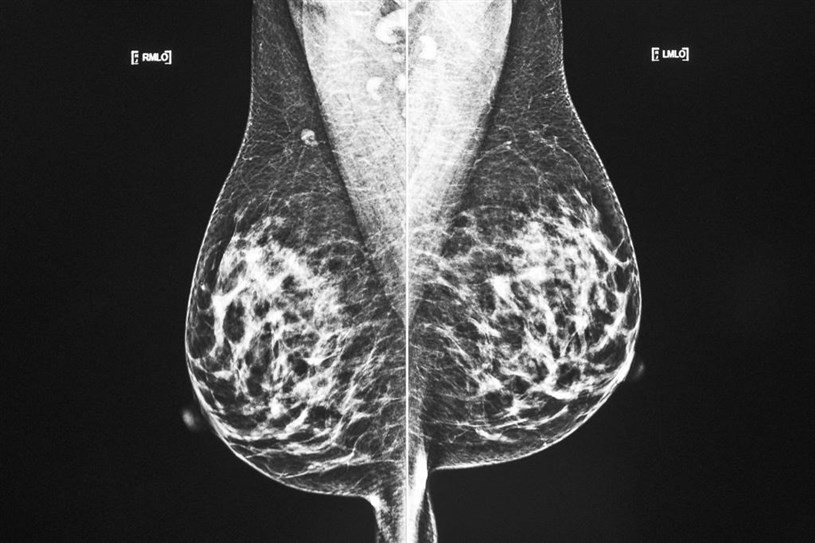

L'obésité pourrait augmenter le risque de cancer du sein chez les femmes dont le risque est déjà plus élevé parce qu'elles sont porteuses des mutations génétiques BRCA1 et BRCA2, prévient une étude à laquelle a participé un chercheur montréalais.